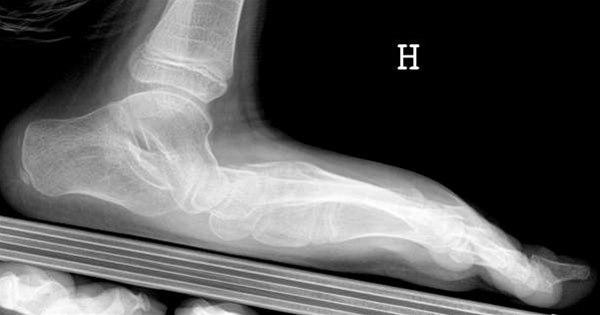

Foten er buet i to retninger, i lengderetningen og tvers over forfoten. Plattfot innebærer at fotbuene er reduserte eller mangler helt. Det skilles mellom myk plattfot, der det er normal fotbue når pasienten står på tær eller ikke belaster foten, og en stiv type der foten er flat hele tiden. Stiv plattfot kan i noen tilfeller gi plager.

Plattfot påvises ved undersøkelse av føttene. Den indre fotbuen siger ned mot underlaget når foten belastes. Ved den vanlige myke plattfot får foten normal fasong når trykket avlastes, som for eksempel når man står eller går på tærne. Dette i motsetning til stiv plattfot der foten alltid er flat, for eksempel på grunn av sammenvoksninger mellom ben i foten.

Røntgenundersøkelser er ikke nødvendig ved plattfot annet enn i de tilfellene hvor det foreligger stiv plattfot og pasienten plages med smerter.

Stiv plattfot fører ofte til plager ved økende alder og økende aktivitet. Spesialtilpassede såler (myke fotsenger) kan være aktuelt ved stiv plattfot. Ved vedvarende plager kan utredning med røntgen være aktuelt. Ved skjelettskader eller nerve og muskelsykdom kan operasjon i foten være aktuelt.